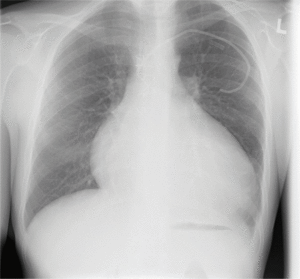

Perforacja prawej komory lub prawego przedsionka w czasie implantacji układu stymulującego lub kardiowertera-defibrylatora (implantable cardioverter-defibrillator, ICD) są stosunkowo rzadkie. Należy zauważyć, że mogą one występować wcześnie po zabiegu lub po upływie kilku godzin lub dni (do 30 dni – subacute perforation) [7-9]. Perforacja może być spowodowana przebiciem ściany prawej komory lub przedsionka przez elektrodę. Częstym mechanizmem jest penetracja ściany serca przez element mocujący elektrodę (active fixation lead). Ze względu na niewielkie uszkodzenie ściany serca krwawienie do worka osierdziowego nie jest nasilone, więc objawy pojawiają się po upływie dłuższego czasu od zabiegu. Przebieg kliniczny może przypominać ostre zapalenie osierdzia. Wysięk w worku osierdziowym może występować okresowo, może też nie być obecny (ryc. 1). Postępowanie obejmuje drenaż osierdzia i zmianę pozycji elektrody pod kontrolą radiologiczną w zabezpieczeniu kardiochirurgicznym (np. w warunkach sali hybrydowej) [1,4,7,8].